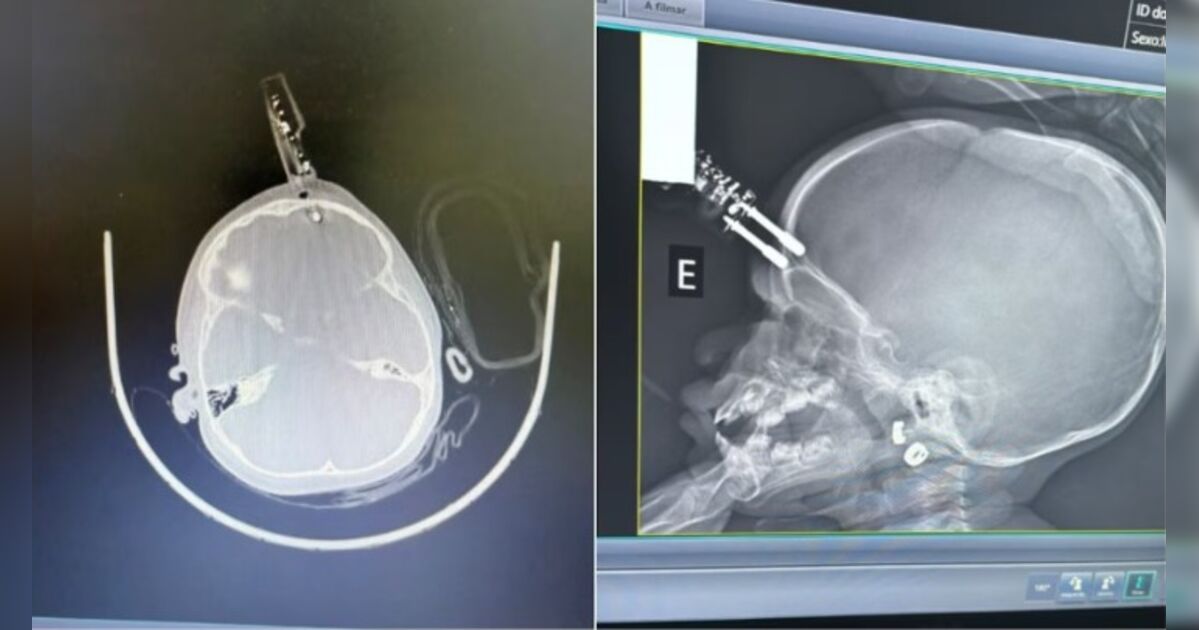

Bebê de 1 ano fica com carregador de celular cravado na testa após cair da cama

ma criança de 1 ano e 4 meses precisou passar por cirurgia após sofrer um grave acidente doméstico em Divinópolis, município localizado a 117 quilômetros de Belo Horizonte. A menina caiu da cama e ac...